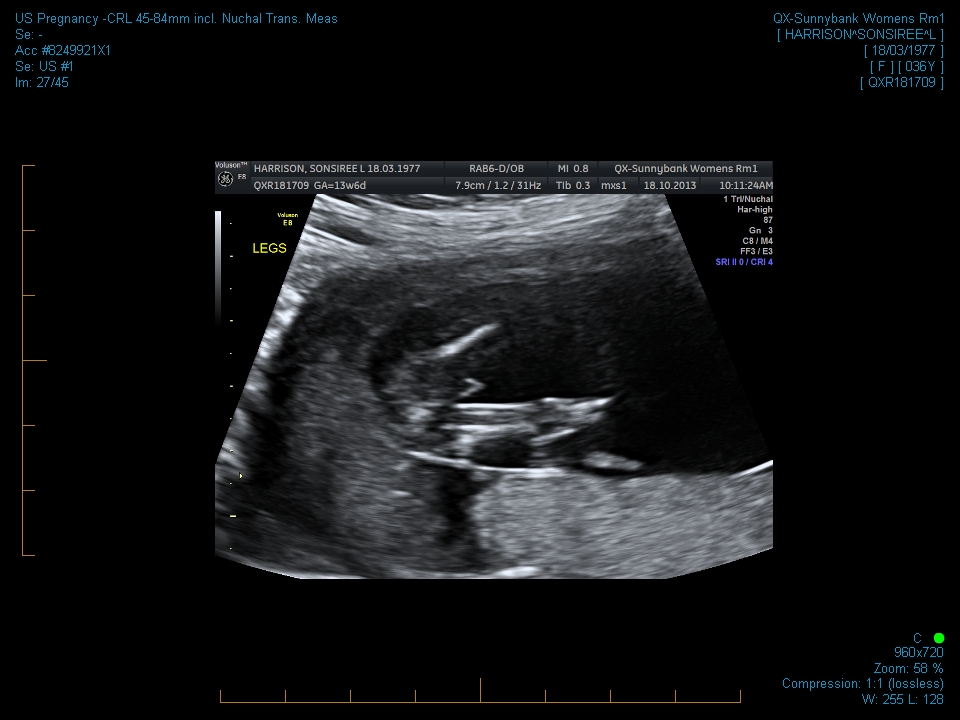

Hi everyone. I am 13w2d and can't figure out if there is a nub in these pics. I also have a potty shot. I know at this age they all have a little something. Can anyone tell me if it is prominent enough to say one way or the other?

Attachment 14828Attachment 14829Attachment 14831Attachment 14832Thanks in advance.